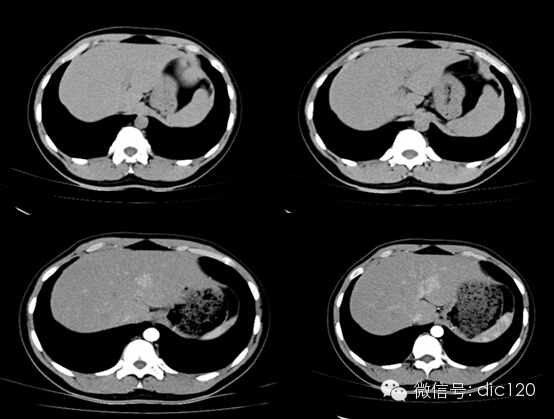

影像表現(xiàn):CT平掃與正常肝組織呈等密度,密度均勻,動(dòng)脈期病灶快速明顯均勻強(qiáng)化,中心見小片狀低密度影(瘢痕),門脈期及延遲期對比劑快速退出呈等密度,中央低密度影延遲強(qiáng)化。MRI腫塊T2WI為稍高信號(hào),中央高信號(hào)。動(dòng)態(tài)增強(qiáng)掃描動(dòng)脈期均顯著增強(qiáng),門脈期輕度增強(qiáng),延遲期瘢痕強(qiáng)化。

FNH具有離心性血液供應(yīng)及二條血液引流途徑。FNH的典型CT表現(xiàn)包括增強(qiáng)早期腫瘤呈彌漫均勻強(qiáng)化,在門靜脈期或門靜脈后期成等密度,病灶內(nèi)可見中心低密度瘢痕及輻射狀分隔,腫瘤周圍有薄而不完整的包膜樣血管。瘢痕是FNH 另一個(gè)重要影像學(xué)表現(xiàn),尤其是延遲掃描瘢痕強(qiáng)化為其特征。